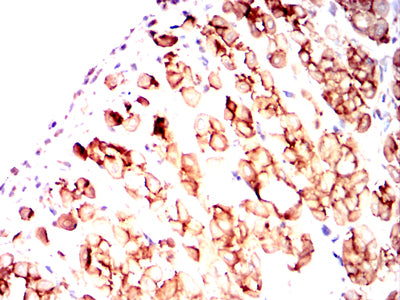

Immunohistochemical analysis of paraffin-embedded human tonsil tissues using CD82 mouse mAb with DAB staining.

Immunohistochemical analysis of paraffin-embedded human rectum cancer tissues using CD82 mouse mAb with DAB staining.